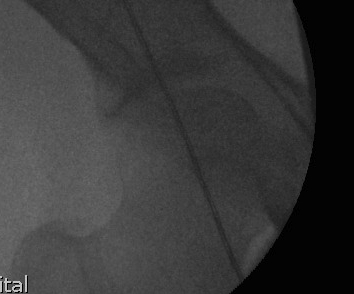

C. Intra-operative check

Use diathermy lead / drop rod

- center femoral head to center on talus

- ensure passes over lateral tibial spine / Fujisawa point